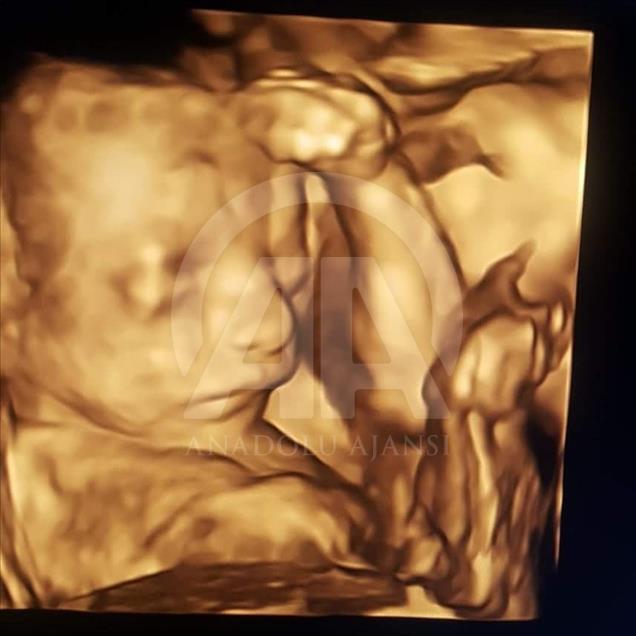

Anne karnındaki bebeklerin ilginç ultrason görüntülerini yakalayan ve bu görüntülerden özel bir köşe oluşturan kadın hastalıkları ve doğum uzmanı Doç. Dr. Gökalp Öner'in, yaklaşık 4 bin fotoğraflık koleksiyonu bulunuyor. Doç. Dr. Öner, AA muhabirine yaptığı açıklamada, sadece bir koleksiyon sahibi olmanın değil, anne ve babalara güzel bir hatıra oluşturmanın mutluluğunu da yaşadığını belirterek, "Doğumdan sonra aileler bizi ziyarete geldiği zaman kendi köşeleri olsun ve orada fotoğraf çektirelim istedik. Böylece, yaklaşık 4 bin ultrason fotoğrafına ulaştık." dedi. ( Müzahim Zahid Tüzün - Anadolu Ajansı )